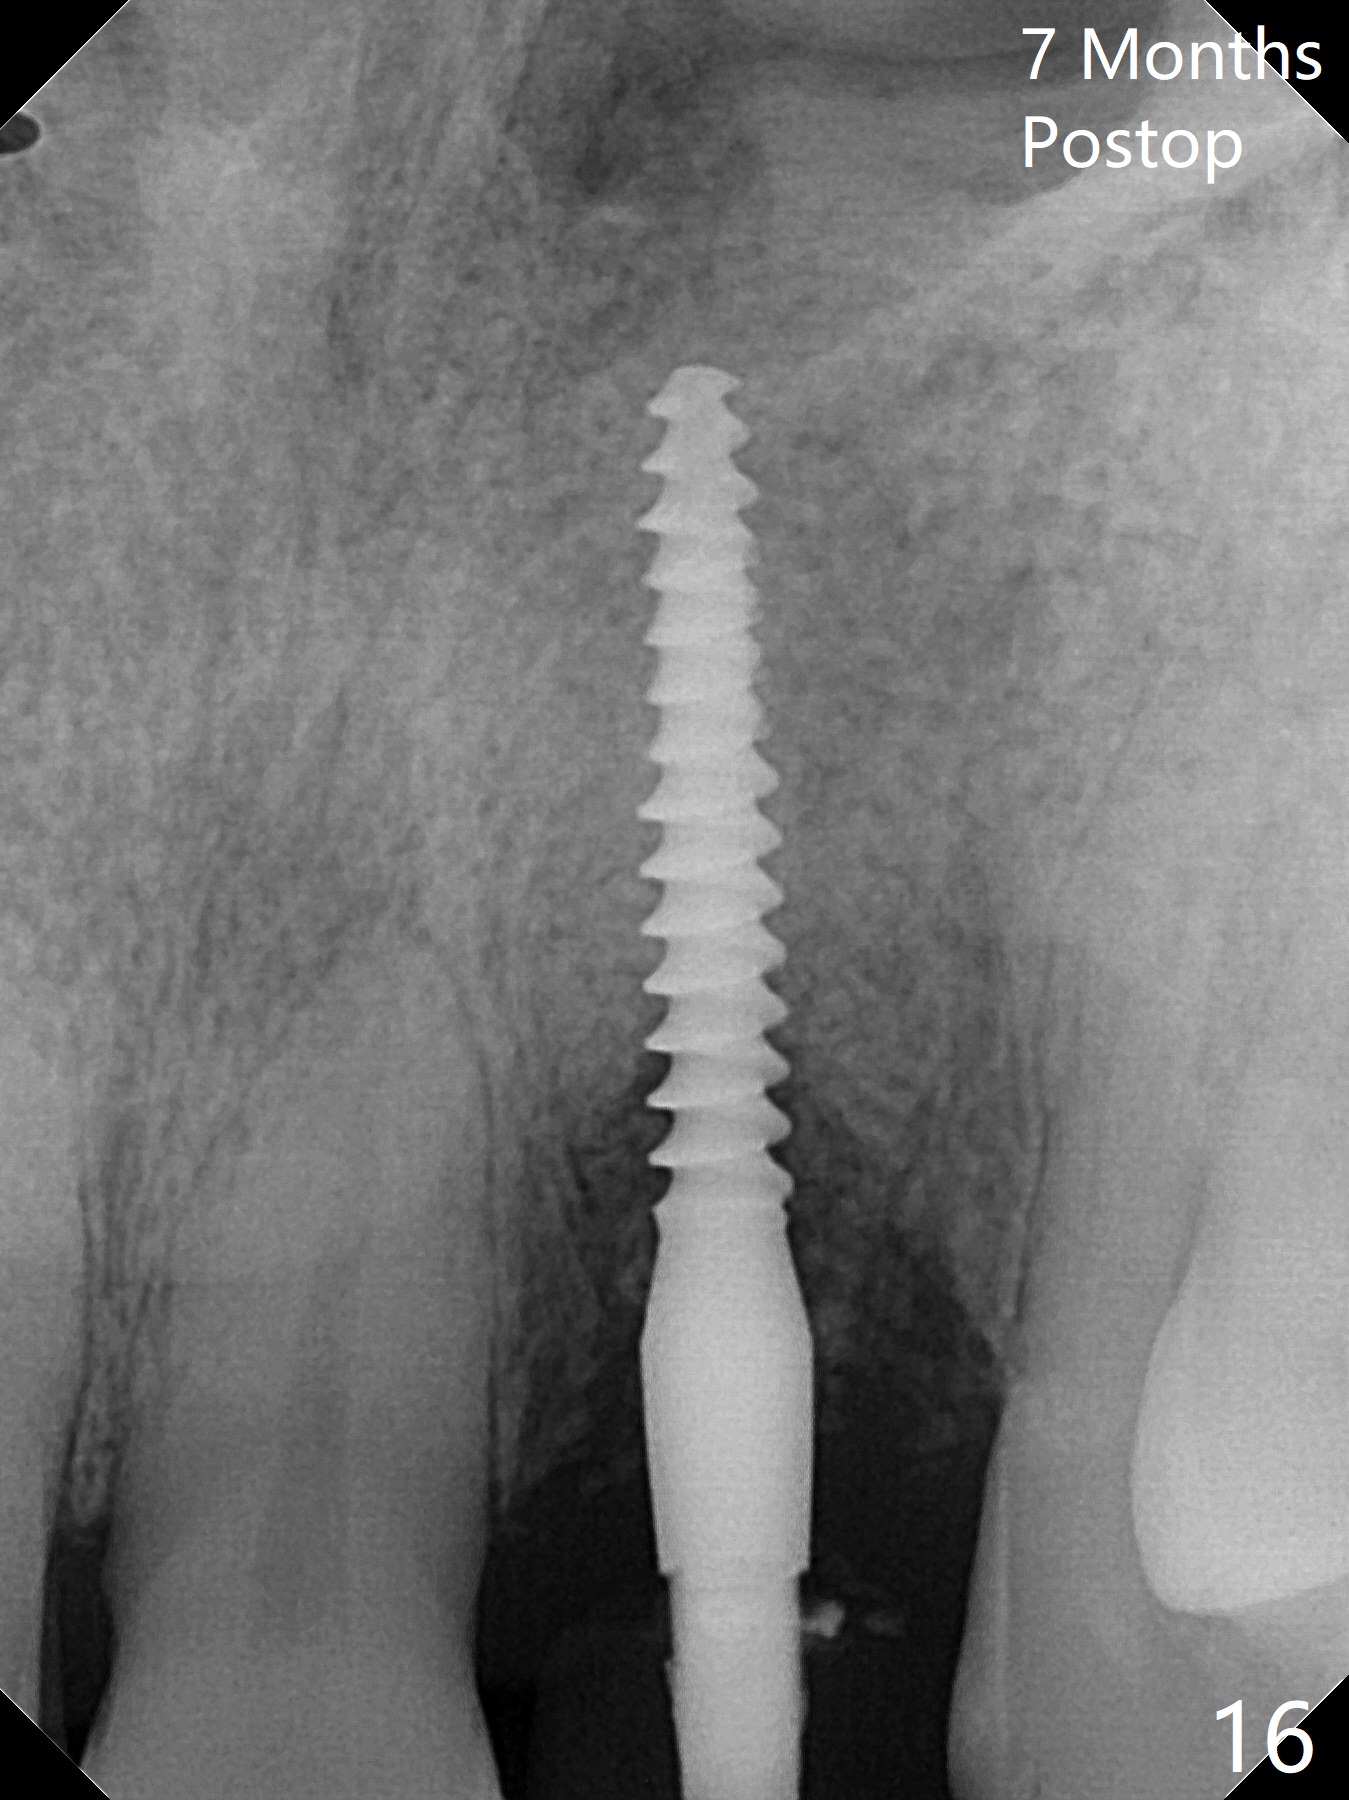

病人回来带来瘘道(图一),不过不会增加难度,病牙去除,它便自动消失。尽管颊侧骨壁完全失去,颊侧牙龈仍丰满(图二),为什么呢?第一,因为粗大牙根存在,第二两旁牙齿,牙槽骨撑着帐篷(侧切牙颊侧牙龈),第三,牙冠。为了防止术后牙龈塌陷,尽量不切开,即刻放置植体(牙根);由于前牙缘故,这次植体不能很大,所以植骨必须过度(over grafting),最后即刻制作临时牙冠,撑住牙龈。这就是所谓每个人进入角色。这个牙根有一种先天性畸形:dens in dent (图三(腭侧观):箭头)。尽管腭侧牙根畸形,腭侧骨壁吸收临床上并不严重,所以钻洞仍偏腭侧。当预定最后钻头还在钻洞时,填入大量粘性骨块(图四:*),细长植体还没有完全卡入鼻底(图五),最后好像可以(图六,七)。植体,骨粉入位(图八),最后临时牙冠出场(图九)。尽管植体小,术后一周临时牙冠仍然可以维持牙龈原有形状(emergency profile,图十:箭头(*:树脂强化牙冠固定))。图十一以不同角度显示瘘道缩小。术后三周取出有些松动的临时牙冠,骨粉虽然还没有被肉芽组织整合,但是显得正常,周围牙龈健康(图十二)。术后4个月牙龈形态正常(图十三),没有触痛;颊侧骨板轻度凹陷(图十四);骨粉仍在原位(图十五)。术后7个月骨粉仍在原位(图十五,十六,但是冠部密度减低(可能骨粉流失,需要牙周或者树脂敷料保护)),没有螺纹暴露。但是牙冠边缘暴露,说明牙龈收缩(图十七,与图十三对比),颊侧骨板仍塌陷(图十八)。插入龈线取得多个目的:修整基台边缘,取模,颊侧牙龈推向颊侧,有利于即将衬里牙冠龈缘进入龈下(图十九)。取模后牙冠边缘(图二十:<)衬里,然后修整,变窄,以便插入龈下,促进颊侧牙龈下降(图二十一,二十二)。术后8个月牙冠粘固前牙龈健康(图二十七,八),牙冠(图二十九)固位后,病人满意(图三十),咬合调整(图三十一),注意腭侧粘固粉流出通道(<)。